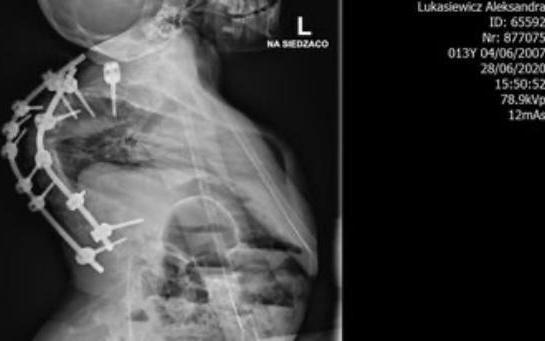

Ola Łukasiewicz, lat 14

14 Ola z głęboką kyfoskoliozą (skomplikowane skrzywienie kręgosłupa) walczy o życie będąc pod respiratorem. Ola jest młodą dziewczynką mającą swoje pasje i chcacą je rozwijać. Jej choroba kręgosłupa sprawiła że życie tej młodej dziewczynki stało się dla niej koszmarem. Nawet najprostsze czynności sprawiają jej mase problemów i potrzebuje osoby dorosłej aby normalnie funkcjonować jako pełnoprawny człowiek. Ale to nie jest teraz istotne ponieważ w tym momęcie choroba zagraża życiu tej wspaniałej dziewczynki.

Dziewczynka ma obecnie BARDZO DUŻE problemy z oddychaniem, a jej narządy są miażdżone przez wykrzywiony kręgosłup, i nie są w stanie normalnie funkcjonować. To nie jest już walka o zdrowie tego dziecka ale o jego życie!